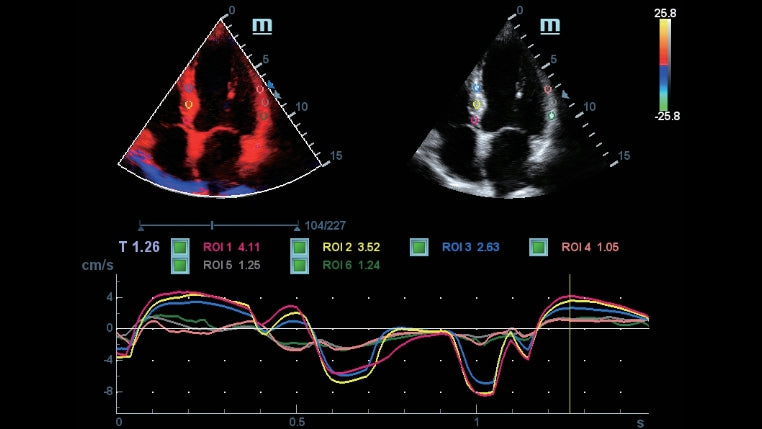

Como una solución de obstetricia, ginecología e imagen general completa, proporciona una interfaz muy robusta e intuitiva. Supera las expectativas de tus rastreos con su sistema de transductores pure crystal